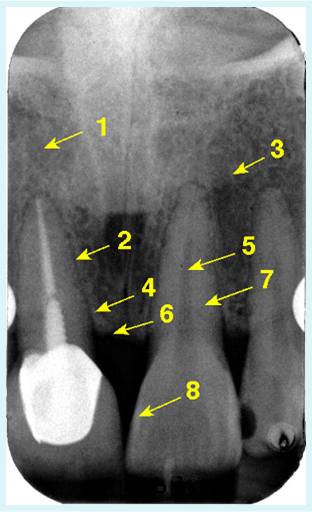

ANATOMIA DENTAL

1.- ESMALTE

EL MÁS RADIOPACO, CUBRIENDO LA CORONA. TERMINACIÓN EN “FILO DE CUCHILLO”.

2.- DENTINA

RADIOPACA, DEBAJO DEL ESMALTE. INVOLUCRA CORONA Y RAIZ.

3.- CEMENTO.

NO SE OBSERVA EN LA RX. POR TENER

IGUAL RADIOPACIDAD QUE LA DENTINA.(NORMALMENTE NO SE VE). ES COMÚN VERLO

EN PATOLOGÍAS DE CEMENTO.

4.- ESPACIO DE LA CAVIDAD PULPAR.

ZONA RADIOLUCIDA, INVOLUCRA LA CÁMARA PULPAR Y LOS CONDUCTOS RADICULARES. SU FORMA DEPENDE DEL DIENTE.

5.- ESPACIO DEL LIGAMENTO PERIODONTAL.

ZONA RL QUE RODEA LA RAIZ DEL DIENTE.SU ESPESOR NORMAL ES DE 1MM O DE 2MMM EN PACIENTES CON ORTODONCIA. ESPESORES MAYORES SON ANORMALES.

6.- LAMINA DURA.

LÍNEA RO QUE DELIMITA AL ESPACIO DEL L.P. CORRESPONDEN A LAS PAREDES DEL ALVEOLO (MESIAL Y DISTAL ).

7.-CRESTA ALVEOLAR (OSEA).

ZONA RADIOPACA FORMADA POR DOS LAMINAS DURAS. LA CRESTA ALVEOLAR DEBE ESTAR A NIVEL DEL L.A.C. O COMO MAXIMO 2MM DEBAJO DE ÉL.

VALORES MAYORES SON ANORMALES